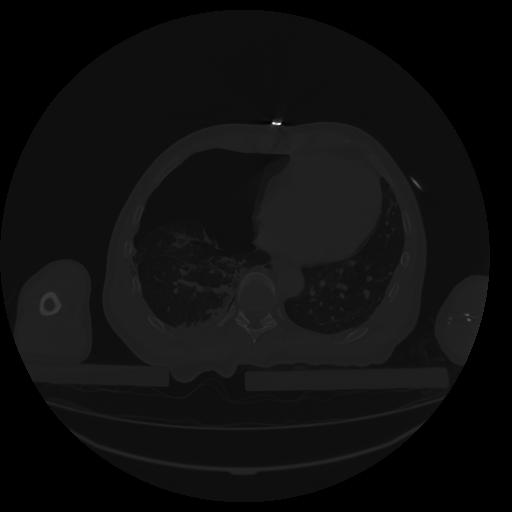

34 CUERPO,CE,Vol,1.0,CUERPO,,